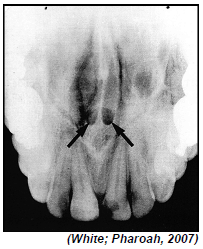

Quais são as estruturas anatômicas indicadas pelas setas na imagem anterior?